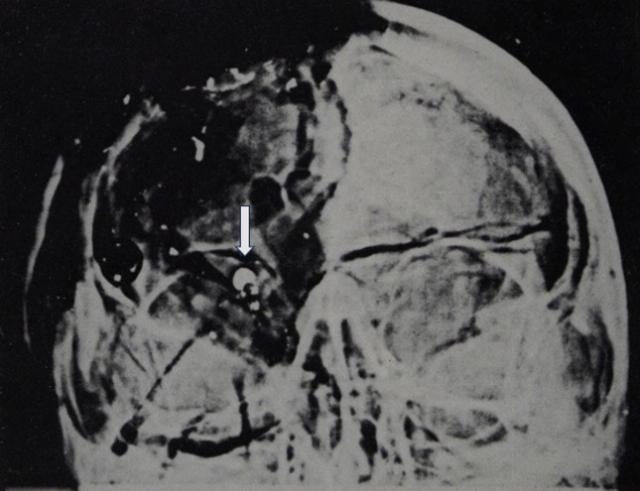

In January 1969, the (Ramsey) Clark Panel finally released its long-awaited (1968) review of the JFK autopsy. That report described a 6.5 mm (nearly circular) cross-section of an apparent bullet fragment inside JFK’s right orbit on the anterior-posterior (AP) X-ray film (Figure 1).1/

Figure 1: This is the anterior-posterior autopsy (AP) X-ray film, often abbreviated “AP.” This view is also sometimes called a “frontal X-ray film.” JFK was lying on his back. The film was placed directly behind his head, with the X-rays entering from the front. The arrow identifies the 6.5 mm object within JFK’s right orbit.

Curiously, although this was by far the largest metal-like object, it had not been described in the autopsy report. In fact, this was its first appearance in history. Furthermore, it had not been removed during the autopsy—and it does not exist in the Archives today—even though the sole point of the X-ray films had been precisely to collect such objects for forensic purposes.

In this anterior-posterior (front-to-rear) skull x-ray, there is an image of what appears to be an extremely radio-opaque, or dense (i.e., lucent) object seen on the x-ray which is purported to represent a metallic fragment—a cross section of the accused assassin’s bullet as it entered the back of JFK’s skull, and then lodged on the outside of his cranium, slightly below the purported entry wound in the bone. (This is the interpretation of both the Clark Panel and the HSCA’s medical panel.) As seen on the AP skull x-ray, this purported bullet fragment is the brightest single object in the image, and therefore represents the densest object depicted in the anterior-posterior skull x-ray—it stands out “like a sore thumb.” It is nearly circular and is about 6.5 mm in diameter. [Vol. 1, p. 49.]